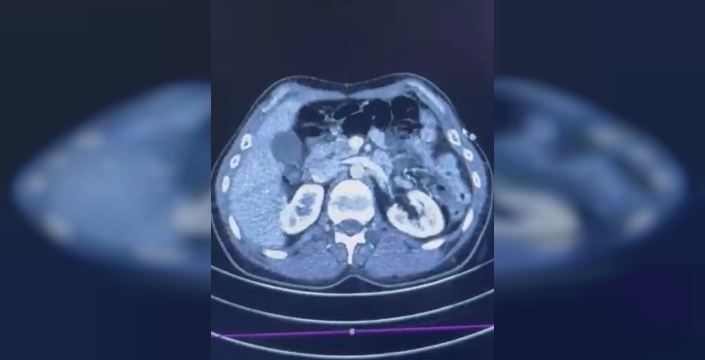

Narkotik Suçlarla Mücadele Şube Müdürlüğü ekipleri, uluslararası uyuşturucu ticareti yapan kuryelere yönelik çalışmalar kapsamında bu operasyonu düzenledi. Şüphelilerin İran'dan Türkiye'ye uyuşturucu getirdiği belirlenerek, yakalanmaları amacıyla harekete geçildi. Operasyonda, S.C. ve R.B.C.'nin Kayseri Şehir Hastanesi'nde yapılan iç beden muayenelerinde, mide kısımlarında 50 adet kapsül bulundu ve bu kapsüllerden toplam 554 gram uyuşturucu madde çıkarıldı.